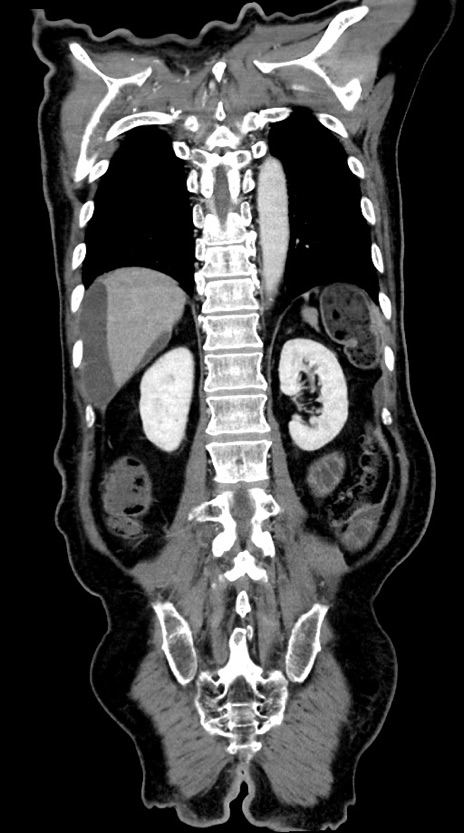

症例28(冠状断像)

【症例】60歳代男性

【主訴】嘔吐

【現病歴】胃癌にて胃全摘後。食思不振が悪化し、夜中に嘔吐することがある。

【既往歴】胃癌、胃全摘、脾摘、胆摘後

【データ】WBC 5900、CRP 10.56